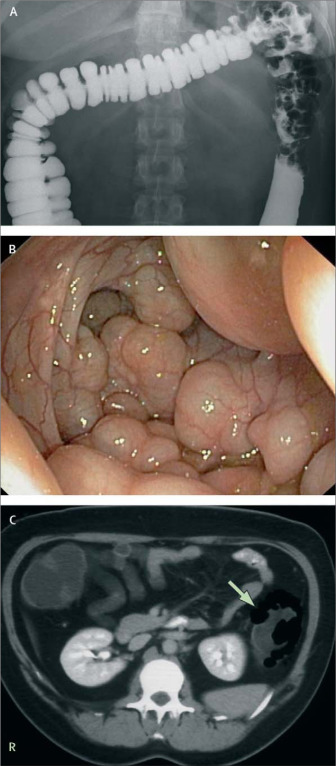

Clinical aspects

Gas production by the colonic microbiota can exert clinical consequences for the host. For example, a common feature of IBS is excessive gas production and flatus, and is associated with bloating and abdominal distension. An absence of bacterial hydrogen recycling can lead towards pneumatosis cystoides intestinalis which is characterized by excessive gas production and the presence of gas filled cysts on the colonic wall [37]. In this instance, an absence of SRB, methanogenic bacteria, and acetogens causes the individual to produce between 5 and 10 times more gas than is usual.

https://www.thelancet.com/journals/lancet/article/PIIS0140673607603626/fulltext

Recycling of hydrogen via dissimilatory sulphate reduction generates hydrogen sulphide, which is a cell signalling molecule of emerging physiological importance [38], but also is highly toxic to colonic cells and is potentially implicated in inflammatory bowel disease, since sufferers of ulcerative colitis have a universal carriage of SRB [39, 40]. The presence of methane in the colon has been linked with colorectal cancer, although the association may be a consequence of the disease rather than causal, since patients with the condition have slower colonic transit times [41]. This would assist growth of methanogens in the gut due to their slow growing nature. Individuals with lactose intolerance have increased gas production, since the defective absorption of lactose in the upper GIT means that lactose reaches colonic bacteria, and is fermented forming gas.